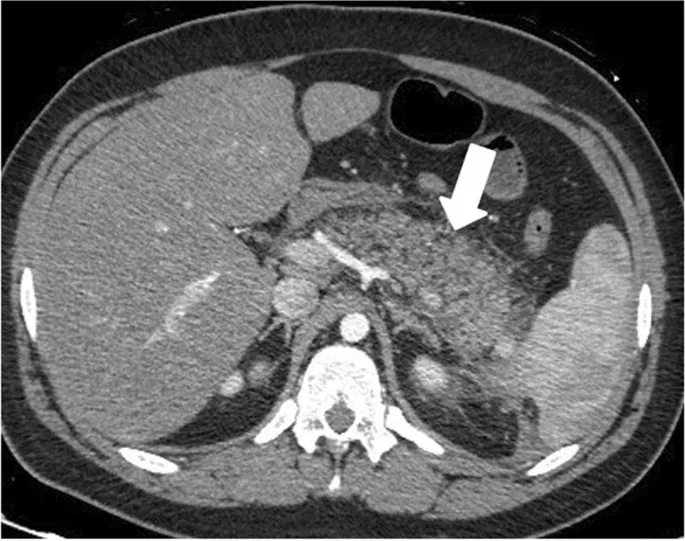

- Contrast-Enhanced CT (CECT):

- Timing: Optimal after 48-72 hours for assessing complications, not for initial diagnosis.

- Role: Identifies pancreatic necrosis (lack of enhancement), fluid collections, and is used for the Balthazar score.